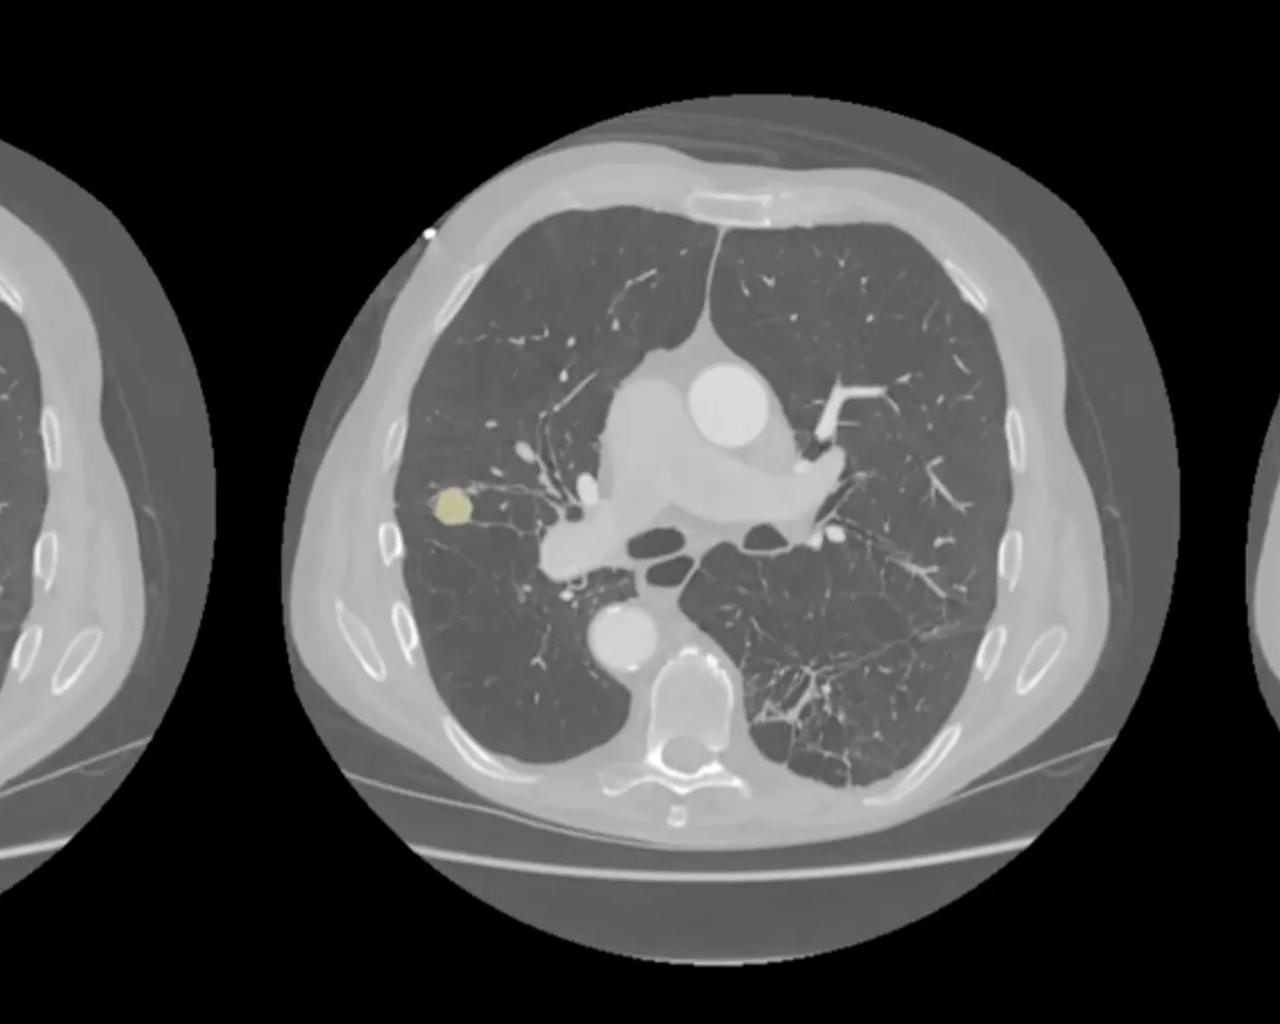

Her ses et udsnit af en CT-skanning af en patients brystkasse. Den gule markering viser en lille knude i lungen, som den kunstige intelligens har fundet, og lægen har bekræftet som kræft. Den kunstige intelligens hjælper her radiologen med at få øje på små forandringer, men den endelige vurdering og diagnose foretages altid af radiologen. Foto: OUH

I 2024 blev systemet for første gang afprøvet i Region Syddanmarks lungekræftscreening. Radiologerne gennemgår først scanningerne på normal vis og får derefter adgang til de fund, som den kunstige intelligens har gjort.

Programmet præsenterer hver enkelt mistænkelig knude, og lægerne vurderer, om de er enige i computerens forslag. På den måde lærer mennesker og maskiner af hinanden.